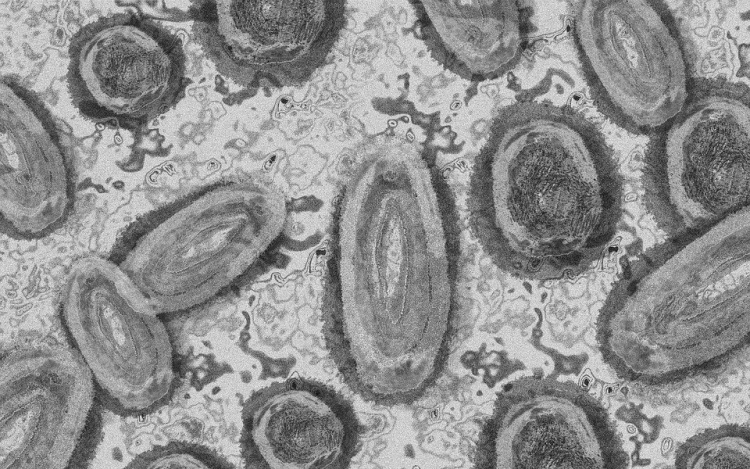

Egy 3 év alatti gyermek fertőződött meg majomhimlővel Belgiumban

Belgiumban egy 3 év alatti gyermek fertőződött meg majomhimlővel - számolt be róla szerdán a Sudinfo hírportál.

Steven Van Gucht, a belga közegészségügyi intézet (Sciensano) fertőző betegségekkel foglalkozó osztályának vezetője azt nyilatkozta, hogy nagyon kivételes esetről van szó, a gyermeket valószínűleg saját szülei fertőzhették meg. Véleménye szerint nagyon ritka, hogy a fertőzés szülőről gyerekre terjed, de előfordulhat. Mint mondta, a gyermekek tünetei általában enyhék.

"A betegségben szenvedőknek nagyon kell vigyázniuk, hogy ne fertőzzék meg gyermekeiket. Akár egy törölközővel is át lehet adni a fertőzést" - magyarázta Marc Van Ranst virológus professzor a helyi sajtónak. Európában eddig 29 fertőzést igazoltak gyermekeknél.

Belgiumban a járvány kezdete óta 671 majomhimlős esetet regisztráltak a Sciensano kedden közzétett adatai szerint. 360 fertőzöttet Flandriában, 236-ot Brüsszelben és 75-öt Vallóniában jegyeztek fel, szinte minden érintett 16 és 71 év közötti férfi.

Harmincegy ember került eddig kórházba, egyikük sem szorult intenzív ellátásra. Halálos kimenetelű esetekről nem érkezett jelentés. A Sciensano tájékoztatása szerint a Belgiumban jelenleg rendelkezésre álló 3220 adag majomhimlő elleni oltóanyagból 1153 adagot használtak fel.

Stefaan Van der Borght, a járványkockázat-kezelési csoport (RMG) elnöke arra figyelmeztetett, hogy "a vakcina nem csodaszer," oltás után is fennáll a fertőzés veszélye. "Kerülni kell a betegségben szenvedő emberekkel való érintkezést, és korlátozni kell a szexuális kapcsolatot" - mondta.